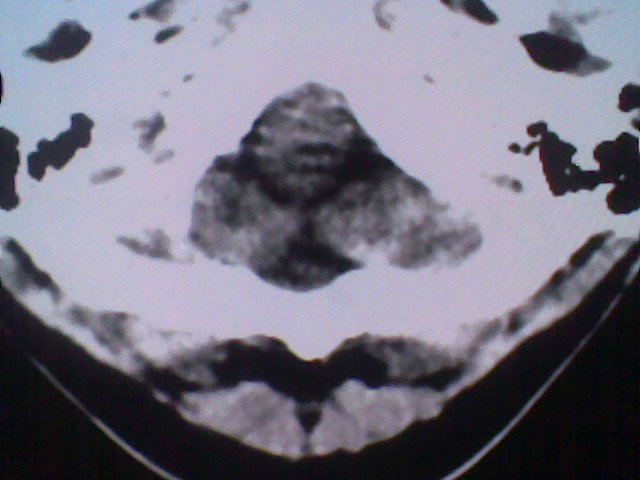

标题: CT21502:这个正常的么?

患者,男,头晕4天来诊,要求ct。

大枕大池合并蛛网膜囊肿。

支持 大枕大池合并蛛网膜囊肿。

考虑大枕大池合并蛛网膜囊肿。

有没有dandy-walker综合征的可能?